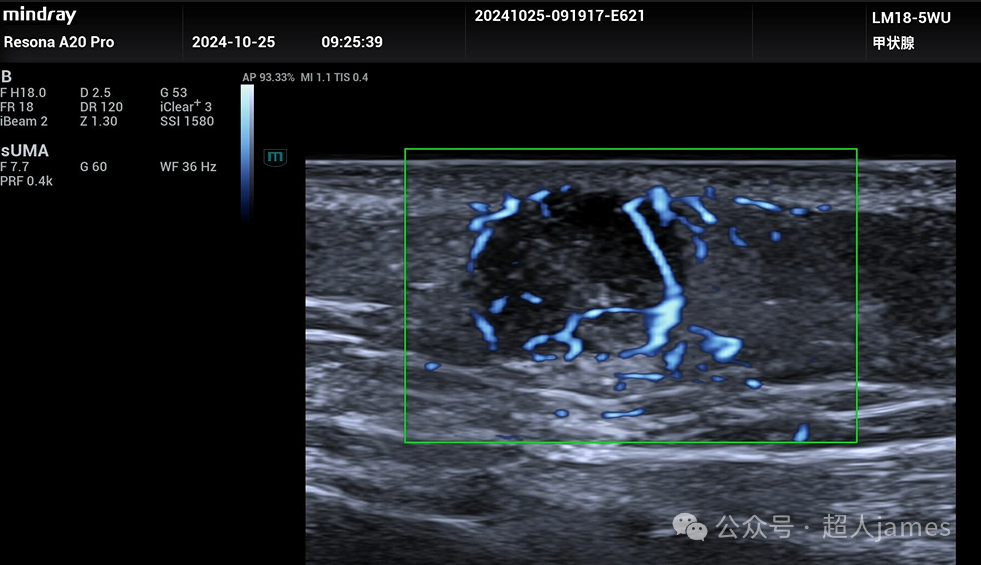

超声表现多样,可以表现为实质片状钙化型、点状钙化灶型、无钙化型、完全钙化型等,边界清晰,后方衰减。利用UMA超微血流成像显示:实质区域可以探及血流信号,这一点是与皮脂腺囊肿、表皮样囊肿的重要鉴别点。